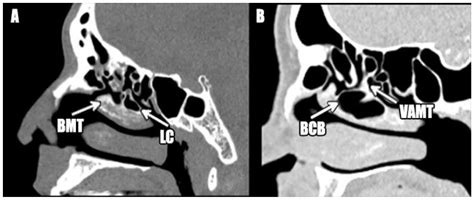

When an air cell develops within the middle turbinate, the structure expands significantly. This expansion is the defining characteristic of a Concha Bullosa. Depending on the size of the air pocket, the enlarged turbinate can press against the nasal septum or the lateral nasal wall, effectively narrowing the nasal passage and obstructing the narrow drainage pathways, known as the ostiomeatal complex, where the sinuses drain into the nose.

Diagnosing a Concha Bullosa typically requires more than a simple visual inspection during a physical exam. While an ENT might suspect the condition using an endoscope—a thin, flexible tube with a camera—a definitive diagnosis almost always relies on imaging. A Computed Tomography (CT) scan of the paranasal sinuses is the gold standard. It provides a detailed cross-sectional view of the nasal architecture, allowing the physician to measure the exact size of the air pocket and determine if it is contributing to sinus obstruction.

CT Scan Detailed imaging to confirm pneumatization and identify potential obstruction sites.

When conservative treatments are ineffective, surgery is often the definitive solution. The procedure is usually performed endoscopically through the nostrils, meaning there are no external incisions. Surgeons typically perform a turbinoplasty or a partial resection of the Concha Bullosa. By removing the lateral wall of the air-filled turbinate, the surgeon can deflate the “bubble,” effectively opening the sinus drainage pathways and restoring normal airflow.